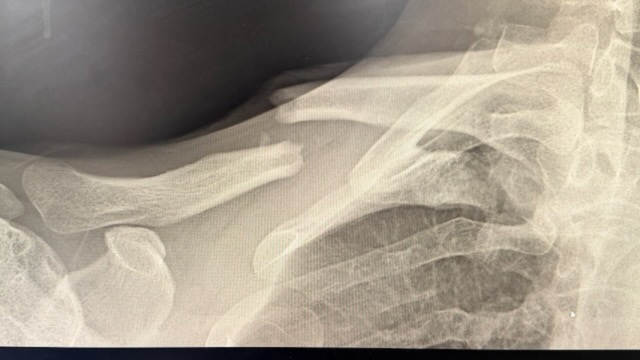

Unfortunately the bone broke at the less protected end instead, so now I have a longer plate.